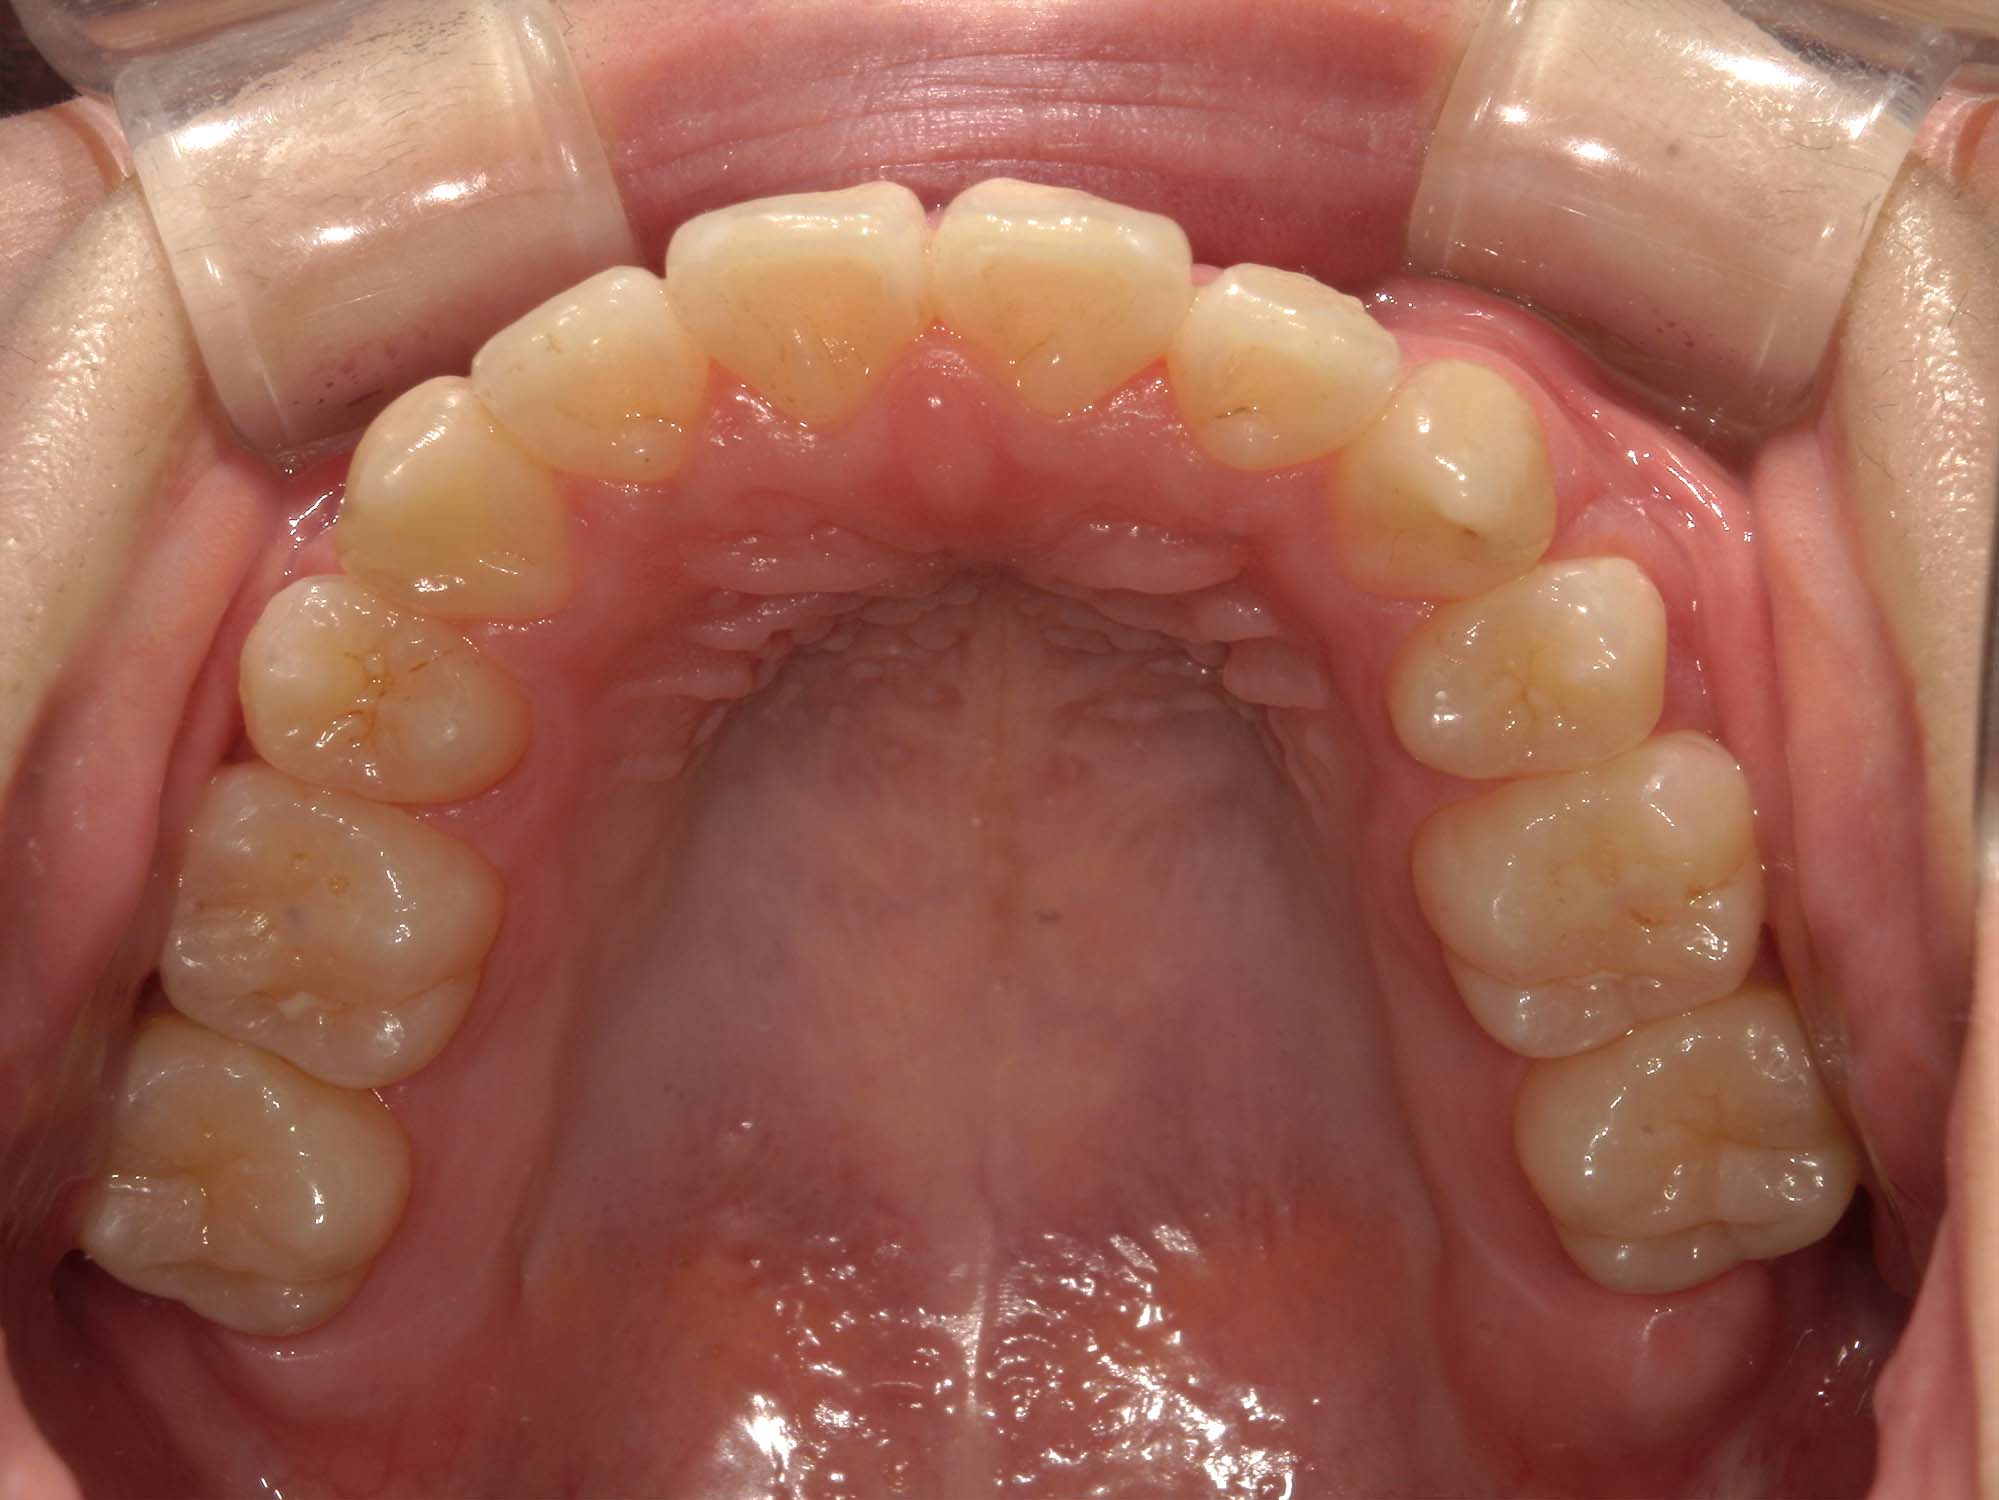

| 年齢・性別 | 15歳の女性 |

|---|---|

| 主訴 | 咬み合わせが逆であること(反対咬合)を気にされて来院された15歳7か月の女性。見た目や機能面の改善を希望されていました。 |

| 治療期間・回数 | 4年4ヶ月・28回 |

| 費用 | 900,000円 |